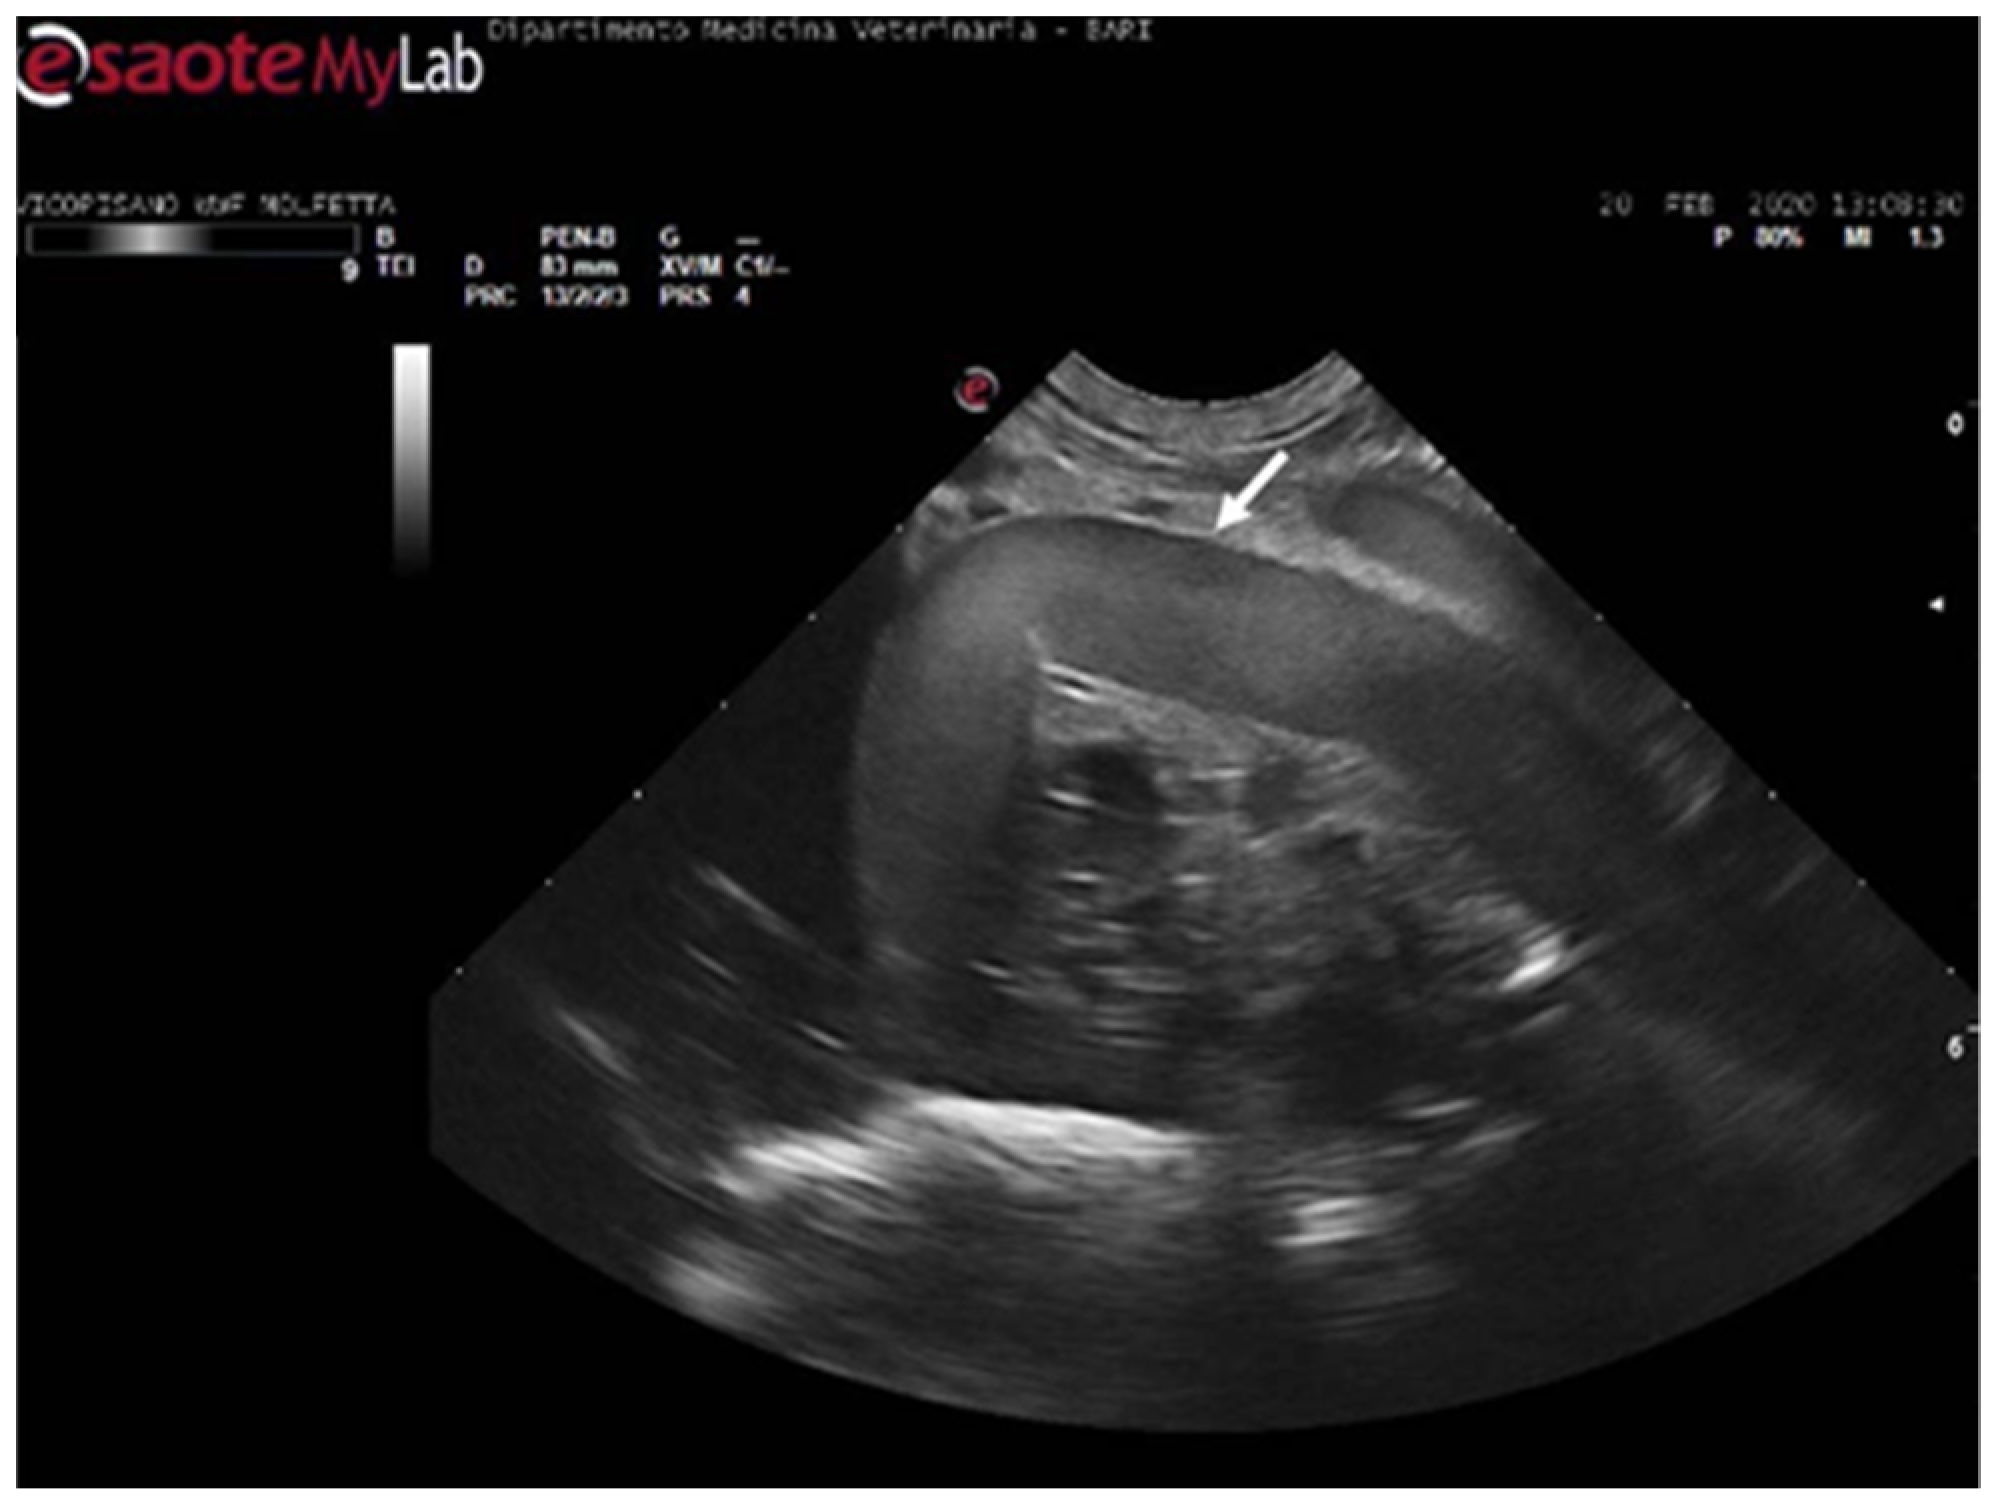

In 11 sea turtles (37, 9%), the ultrasound examination revealed the presence of emboli in various districts, often in limited quantity. Those emboli varied in size but were generally considered microemboli. They were observed to enter the bloodstream in a cascade, resulting in slower and intermittent blood flow on Color Doppler ultrasound. Ultrasonography provided distinct visualization of the liver parenchyma and its vessels, allowing for a clear view of the intestinal loops and their associated circulation. The larger emboli were consistently found adhering to the vessel walls, while smaller emboli occasionally detached and flowed into the bloodstream (Figure 5) (Video S1).

The patients displaying these ultrasound findings were placed in the mild category following Parga’s method [17]. In some animals within this group, ultrasonography revealed emboli in multiple areas compared to those identified on radiographs. Additionally, in a turtle that appeared radiographically negative, ultrasound exams detected the presence of microemboli in the renal arteries on both sides, as well as in the left subclavian artery (Figure 6).

In four turtles (13, 8%), the ultrasound examination revealed a significantly slow blood flow, but no flow was detected using Color Doppler ultrasound. The renal vessels and subclavian vessels, which were closer to the acoustic windows, were easily identified. However, examination of the vessels and the coelomic cavity through the ventral cervical acoustic window was challenging due to significant gas-related disorders. Consequently, visualization of the aortic arch and the heart was precluded. Similarly, it was impossible to locate the mesenteric vessels and differentiate the hepatic parenchyma along with its associated circulation. The presence of larger emboli, some up to 5 mm in size, hindered the visualization of vessel walls, and the gas-induced artifacts, such as comet tails, were so pronounced that they masked the view of tissues and vascular regions (Figure 7) (Video S2). Those ultrasound images have been a consistent finding in the subjects previously categorized by radiographic exams as having moderate GE, implementing Parga’s method [17].

Figure 5. Ultrasound scan from the right prefemoral window shows an aggregate of medium-sized microemboli adhered to the wall of the iliac vein (white arrow), releasing very small emboli into the bloodstream (empty white arrows). The black arrow indicates the renal parenchyma.

Figure 6. Ultrasound scan from the ventral cervical window revealing an aggregate of sizable microemboli (empty white arrow) in transit within the bloodstream of the left subclavian artery.

Figure 7. Ultrasound scan from the right prefemoral window revealing several clusters of large emboli attached to the hepatic vessels (empty white arrows). The artifacts generated by their presence (white arrow) make it challenging to visualize deeper structures.